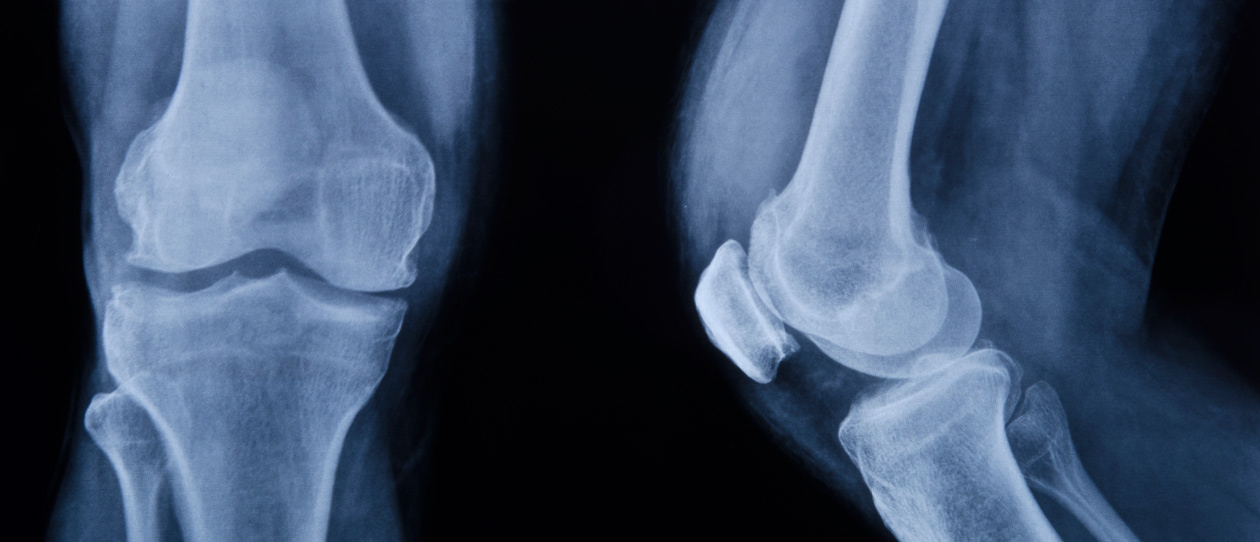

is an innovative treatment for mild to medium bone and cartilage degeneration.

It uses the stem cells collected from a patient’s own fat to treat the painful orthopedic ailments of knees, hips, shoulders, ankles and other joints.

This treatment uses the regenerative components of your body’s fat cells to repair the degenerative conditions of bone and cartilage that may arise due to ageing or trauma.